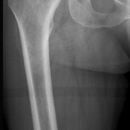

Proximaler Oberschenkel a.-p. (1. Ebene)

Fraktur, Z.n. Osteosynthesematerial

Rückenlage

aufzunehmendes Bein gestreckt und innenrotiert

ZS senkrecht auf Objekt- und Detektormitte

Länge voll ab Spina iliaca anterior superior, lateral Hautgrenze auf Höhe Trochanter major

Bei Erwachsenen soll das Hüftgelenk a.p. orthograd mit abgebildet sein.